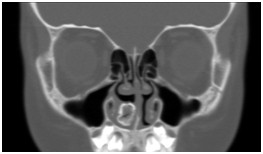

影像科在五官疾病诊治中的严谨、专业,全面开展眼、耳、鼻、喉精细化检查及诊断。

鼻窦(病例-异物):